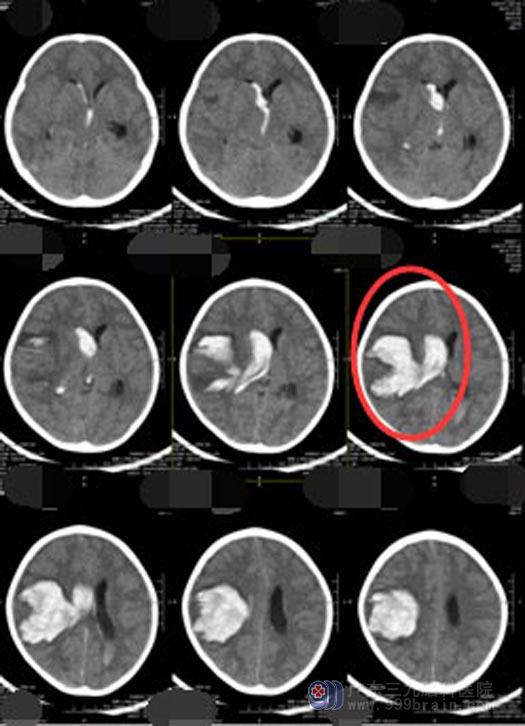

家人立即带她到当地的医院检查,头颅CT检查显示脑内血肿形成并破入脑室。此时珊珊已经深昏迷、气管留置插管,病情非常危急,需要马上开颅手术,由于当地医院的医疗条件有限,医生建议珊珊的父母立刻转院。

家人当机立断,连夜将珊珊送到了广东三九脑科医院神经外五科。入院时,她的双侧瞳孔已散大,不能发声、不能睁眼,刺痛肢屈。珊珊已经出现了脑疝,随时可能呼吸心跳骤停。当天值班的李医生立即向鲁明主任汇报患者病情并开通了绿色通道,在短短的半小时内就将珊珊送入了手术室,在全麻下行“血肿清除术+去骨瓣减压+气管切开术”,手术持续近6个小时。手术后,珊珊的瞳孔对光反射灵敏,“暂时算是把命保住了”。